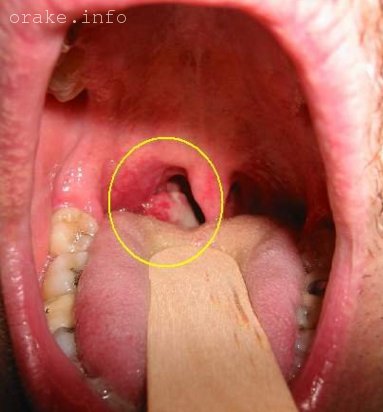

Рак носоглотки – фото: